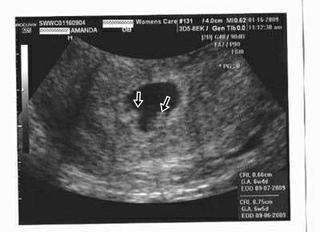

Já jsem na ten google koukala taky a našla jsem tam přesně fotečku, kterou mi doktor ukazoval. Dokonce jsem koukala, že i týdny a dny vcelku souhlasí s mými. Je tam 6tt5d a já včera měla 6tt4d. Posílám Ti ji. Takhle přesně si tam Ti bobci hověli. Akorát na té mojí fotečce ty plody byli trošičku více zřetelnější.